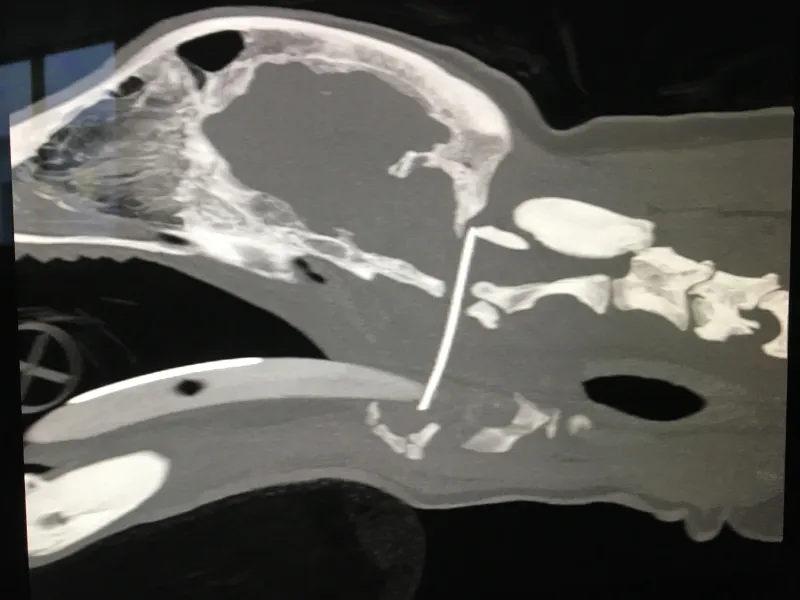

Toby was referred to the Hospital for Small Animals, where a CT scan was used to evaluate any major damage to Toby’s spinal cord. During surgery, they used specialist X-ray equipment to view the needle in real-time.  The innovative approach allowed the surgeons to carefully remove the object without the need for an invasive operation.

CT showing the needle placement